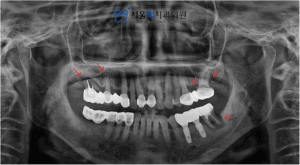

처음 내원하셨을 때,

환자분의 파노라마 방사선 사진입니다.

화살표로 표시된 치아를 보시면

치주질환으로 인해 치조골의 높이가

내려간 것을 볼 수 있는데요.

양측 다 좋지 않았으나 왼쪽(사진에서 오른쪽)

어금니를 먼저 저작기능을 회복시켜드려서

편하게 식사하실 수 있도록 해드리고,

추후 오른쪽(사진에서 왼쪽) 어금니까지

적절한 치료를 받으시는 것으로 계획을 세워드렸습니다.